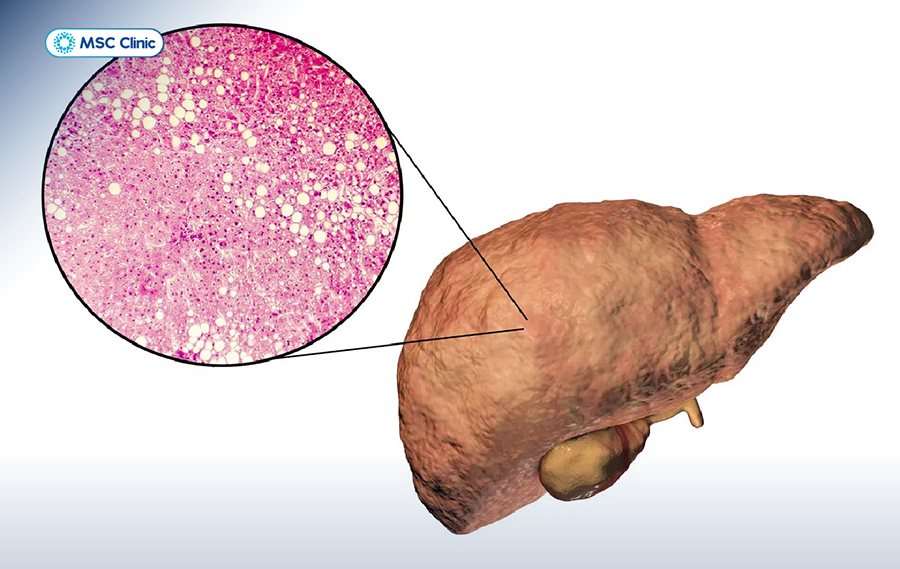

Gan nhiễm mỡ là một tình trạng phổ biến, xảy ra khi có quá nhiều chất béo tích tụ bên trong các tế bào gan. Tình trạng gan nhiễm mỡ thường được chia thành 3 giai đoạn chính, dựa trên mức độ tích tụ mỡ và tổn thương gan:

Tóm lại, dù là do rượu hay không do rượu, gan nhiễm mỡ đều là kết quả của sự mất cân bằng trong chuyển hóa chất béo, dẫn đến mỡ bị ứ đọng và gây tổn thương gan.